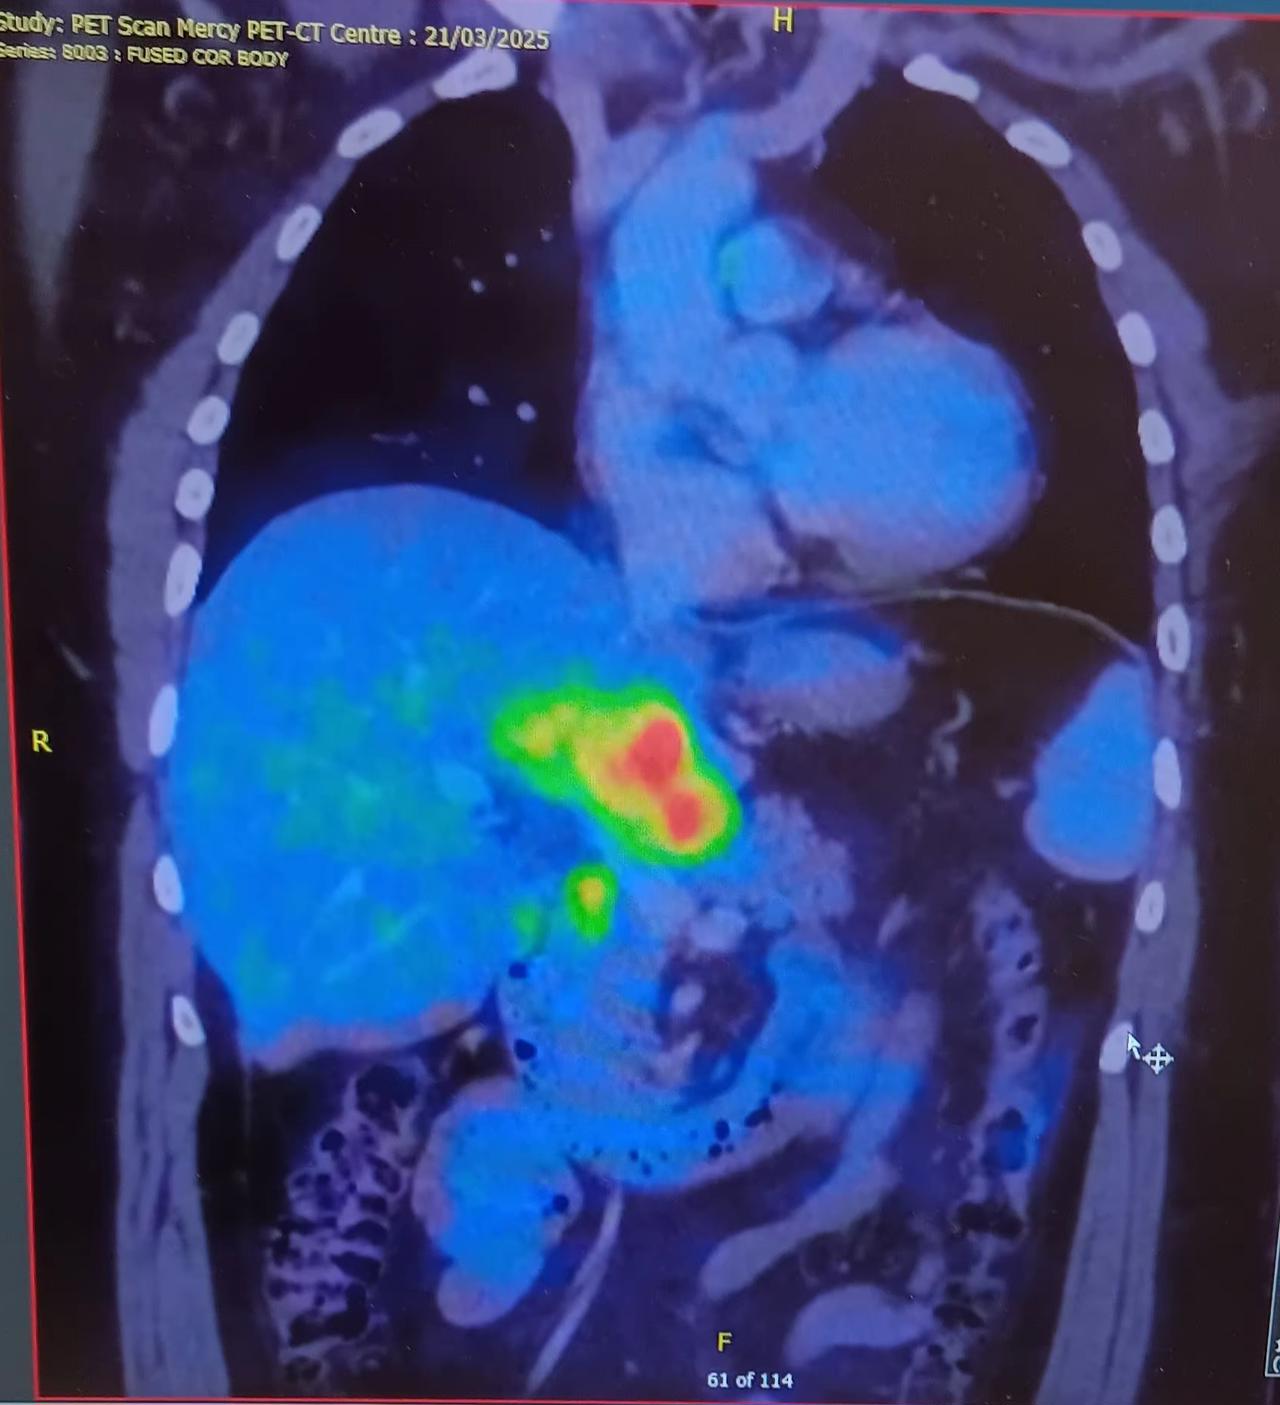

Main image

I have cancer in my liver, lungs and some nodular shizz. Tumour Willis 2 will will be the name for small one in lung. Tuma Thurman the Third will be nodular one. Amy Tumour (pictured) will be the name of the Liver one (Since, like Schumer, it's already been done before and is just plagiarism by now. Whoa, sick burn of a comedian much, much better than me!). It's all bowel cancer. They hope it shrinks for surgery but we are moving into a more "keep me alive longer" as opposed to a possible "cure" now. Neat.